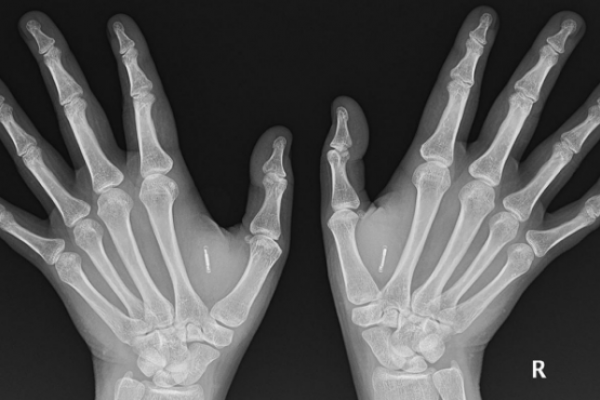

Uno de los motivos más frecuentes en las consultas de urgencias de los hospitales son las fracturas y otras patologías agudas traumatológicas.

Las patologías agudas traumatológicas suponen un reto para cualquier facultativo que desarrolle su actividad en un servicio de urgencias; de hecho, en la mayoría de los países desarrollados, los médicos implicados en la atención de las urgencias traumatológicas provienen de diferentes especialidades.

Aprender a identificar y atender las lesiones más frecuentes en el miembro superior .

Módulo 1. Urgencias Traumatológicas del miembro superior

1.2. Muñeca y mano (salvo dedos)

1.2.13. Lesiones tendinosas

1.2.14. Fracturas y luxaciones de los dedos

1.2.15. Amputaciones de los dedos

1.2.16. Cuerpos extraños en muñeca y mano

1.2.17. Infecciones en la mano